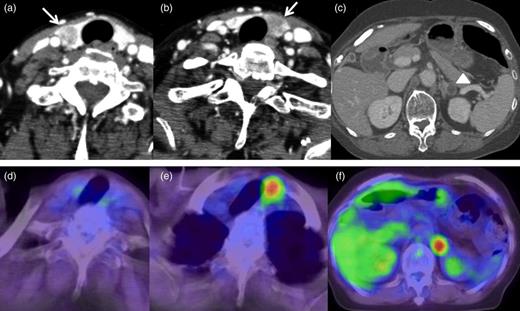

A 72-year-old-woman with a history of rectal cancer was admitted to the Doaikinen Hospital, Tokyo, Japan, in November 2013. She had undergone radical surgery for rectal cancer in July 2009. The pathological examination revealed a moderately differentiated adenocarcinoma with lymphatic and venous invasion, and the pathological grade was T3 N1 M0, stage IIIb, according to the International Union Against Cancer tumor-node-metastasis (TNM) 7th classification. She received adjuvant chemotherapy with capecitabine, but right lung metastasis was detected in October 2010 on follow-up CT scan. After subsequent chemotherapy of irinotecan with tegafur–gimeracil–oteracil potassium (IRIS), she underwent partial resection of the right lung in March 2011. She did not receive adjuvant chemotherapy post-operation, and right lung metastasis was detected again in January 2012. Chemotherapy of IRIS with panitumumab (Pmab) was initiated, but the lung metastasis progressed, and right adrenal gland metastasis appeared in August 2012. Both metastases were assessed to be surgically resectable, so partial resection of the right lung was performed in September 2012, and right adrenalectomy was performed in November 2012. Adjuvant chemotherapy of oxaliplatin with fluorouracil and folinic acid was introduced after the operation, but carcinoembryonic antigen and carbohydrate antigen levels gradually increased (Fig. 1). Follow-up CT scans detected nodules in the left adrenal gland and bilateral thyroid gland in October 2013 (Fig. 2a–c). The serum level of thyroid-stimulating hormone was 1.79 μU/ml, Free-T3 was 2.83 pg/ml, Free-T4 was 1.10 ng/dl and thyroglobulin was 101 ng/ml. Fine-needle aspiration was performed on the nodules of the thyroid gland, and metastasis of rectal cancer was highly suspected histologically. 18F-fludeoxyglucose positron emission tomography (18FDG-PET) scan revealed high uptake of 18FDG in the nodule of the left lobe of the thyroid gland, and in the left adrenal gland (Fig. 2d–f). No metastasis in the other organs was detected on the radiological findings, and hence we decided to perform surgical resection for the tumors of the thyroid gland and left adrenal gland.

CT scans and PET scans of the neck and abdomen. (a and b) CT scan of the neck detected low-density nodules in bilateral lobes of the thyroid gland (arrows). (c) CT scan of the abdomen detected a low-density nodule with clear border in the left adrenal gland. (d) PET scan did not show abnormal uptake of 18FDG in the nodule in the right lobe of the thyroid gland. (e) PET scan showed abnormal uptake of 18FDG in the nodule in the left lobe of the thyroid gland. (f) PET scan detected abnormal uptake of 18FDG in the nodule in the left adrenal gland.